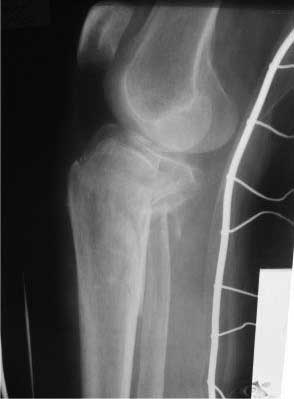

Уважаемые колллеги! Женщина 73 года, травма в результате падения с высоты своего роста, получила закрытый оскольчатый внутрисуставной перелом проксимального отдела большеберцовой кости. Сельский житель, ничем до травмы особо не болела, аткивная. Единственная жалоба на появление гематом и ран даже при незначительных ушибах. Рентгеновские снимки прилагаю, если есть необходимость, позже выложу КТ. А вот кожа... пальпаторно очень тонкая, практически пергамент, сухая, тургор снижен (есть фото). Прошу вашей помощи. Учитывая состояние мягких тканей, оскольчатый перелом большеберцовой кости на большом протяжении, есть вопросы: -чем фиксировать; - как (MIPO?) и в какой последовательности; -когда начинать операцию? Заранее благодарен

Перелом нестабильный, двухмыщелковый (Schatzker VI). Учитывая возраст больной и состояние мягких тканей (судя по фотографии, выраженные расстройства микроциркуляции), первым этапом стабилизируйте перелом (скелетное вытяжение за бугор пяточной кости), в течение дней 10 - инфузионная вазотропная терапия (трентал, но-шпа, клексан).

2. В аппарате для уточнения анатомии повреждения (костного) нужно выполнить КТ (лучше в аппарате, а не до него). Там скорее всего увидим не только импрессию наружного мыщелка, но и перелом внутреннего со смещением.

Следовательно начинать фиксацию надо с внутреннего мыщелка и не снимая аппарата(доступ 1 задне-медиальный, ORIF, DCP 3.5 мм, LC-DCP 3.5 мм, но лучше LCP 3.5 мм), затем восстанавливать наружный мыщелок (доступ 2 - наружный парапателлярный с прямым контролем репозиции суставной поверхности, ORIF суставного компонента, LCP-PLT 5.0 мм). На втором доступе действительно можно немного сэкономить - протолкнуть пластину над костью и зафиксировать дистально из отдельного минидоступа или проколов.

На боковом рентгене, явный задний смещенный компонент. КТ поможет увидеть "вершину" перелома, куда надо поставить антискользящую пластину из заднего или задне-медиальнего доступа. Для стабилизации боковой колонны традиционный боковой доступ через Girdle tubercle с длинной блокирующей пластиной. Одна задняя подпорка не удержит медиальную колонну, требуется длинная медиальная пластина.